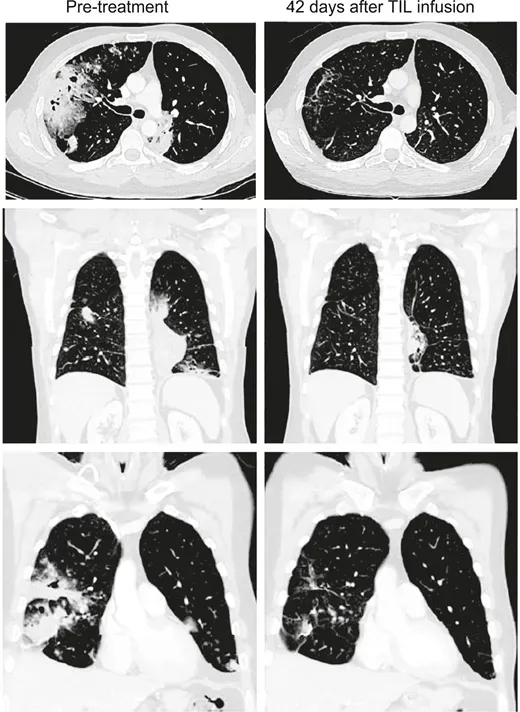

《癌症探索》杂志曾报道一则经典案例:一名41岁IV期粘液性肺腺癌男性患者,携带KRASG12D突变,肿瘤突变负荷(TMB)为3.3mut/Mb,PD-L1表达为0%。其接受TIL治疗前,CT显示治疗反应持续时间仅1.1+个月;而接受Lifileucel治疗6周后,治疗反应持续时间延长至26.2+个月,且疗效随时间推移逐渐加深,至输注12周时,部分缓解(PR)率高达81%(详见下图)。

▲图源“Cancer Discov”,版权归原作者所有,如无意中侵犯了知识产权,请联系我们删除